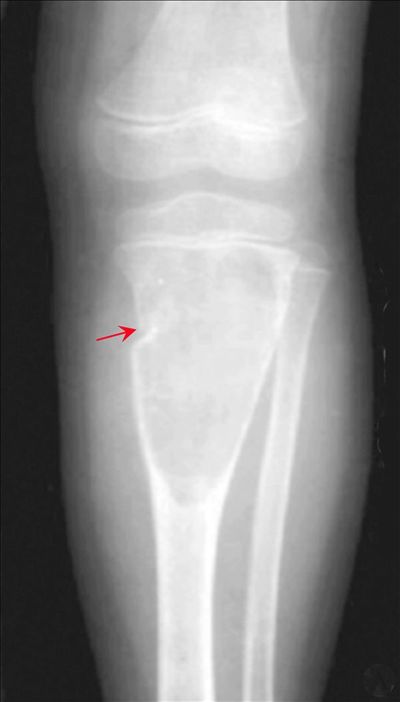

病理性骨折骨囊肿并骨折-CT

【影像表现】:X线正位片示胫骨上端膨胀性类圆形囊状透光区,伴病理骨折及折片凹陷征(↑)。

【影像诊断】:病理性骨折,骨囊肿并骨折。